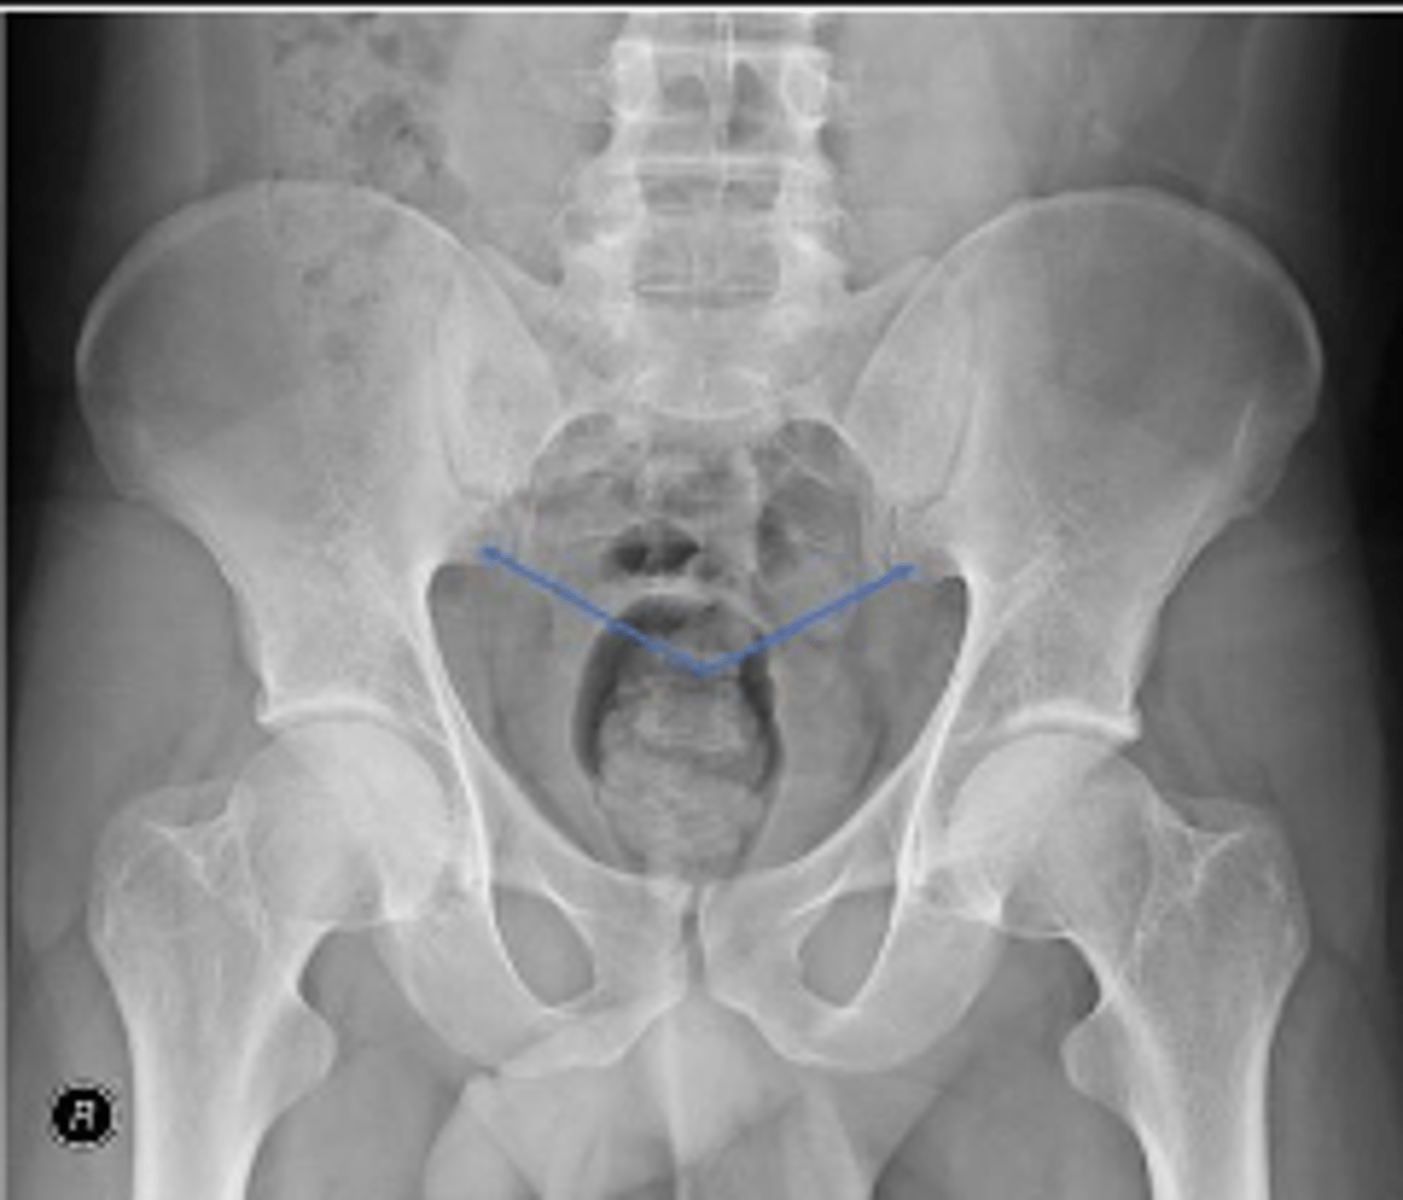

AP pelvis or bilateral hips

What is the name of the radiographic view?

What are the arrows pointing to?

What is the anatomical structure in between the lines?

What is outlined?

What joint space are the arrows pointing to?

What joint space is the arrow pointing to?

Which IVD space is indicated by the arrows?

PSIS

Right L5 transverse process

Coccyx

Left obturator foramen

Left superior pubic ramus

Left inferior pubic ramus

AIIS

Right ischial tuberosity

Right pelvic teardrop

Phleboliths

Greater trochanter of the right femur

Right S3 superior border of the sacral foramen

Greater trochanter of the left femur

L3/L4 IVD space

What IVD space is indicated by the arrows?